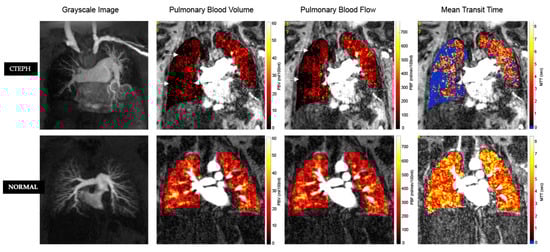

3. Pulmonary Perfusion

3.2. Dual Energy CT, DECT

3.3. MR Perfusion